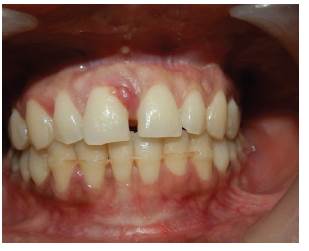

En el exámen estomatológico se observó lesión tumoral unilobular en el maxilar superior localizada a nivel de encía marginal vestibular por mesial de órgano dental 11, de base sésil, consistencia firme y blanda, de 3 mm de diámetro, de superficie eritematosa, con ligero sangrado al mínimo contacto, correspondiendo con las características clínicas descritas por Rebolledo y cols en 2015 11 (figura 1A). No se observa sobreinserción de frenillo labial superior que justifique la aparición de diastema entre los dos órganos dentarios anterosuperiores.

Se realizó evaluación de la condición de los tejidos periodontales a nivel de órgano dentario 11 mediante una sonda periodontal tipo Williams y se obtuvo profundidad de sondeo de 10 mm (figura 1B). Se evidencia margen gingival sin recesiones o hiperplasias en otras zonas; no se observa presencia de placa bacteriana abundante, cálculos supragingivales o caries que actúen como factor irritante asociado.